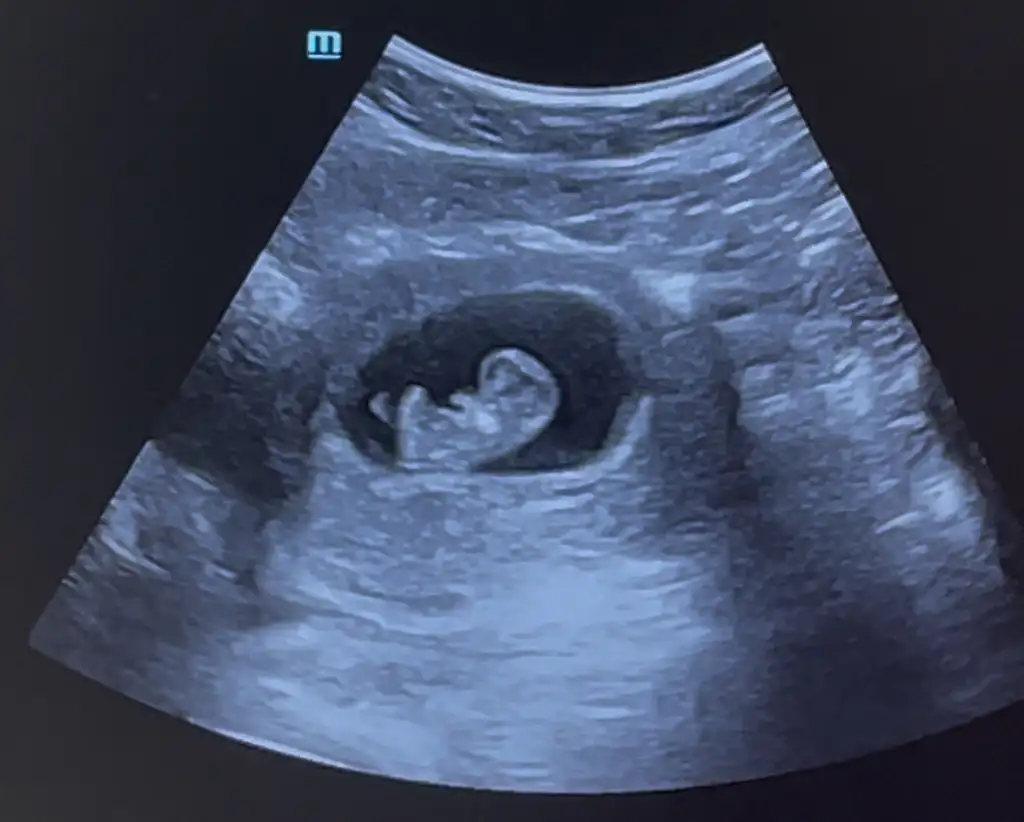

Ben en son 7+4te gitmistim, et parcası gibi bir seydi, bir de dün gittim 8+5te inanamadım gördüğüm şeye

Eli kolu oynayan hareket eden bir seye dönüsmüs, kalbi falan duydugumda da cok idrak edememistim ama dün hareket eden ve nispeten bebek formunu almıs bi seyi görünce eve gidene kadar hüngür hüngür agladım

Yani demem o ki simdi kontrole gittiğinizde gördügünüz sey sizi gercekten hayrete sokacak, Allahın mucizesi

Allah su anda hamilelik yasayan herkese yavrularını saglıkla sıhhatle afiyetle kucagına almayı nasip etsin insallah